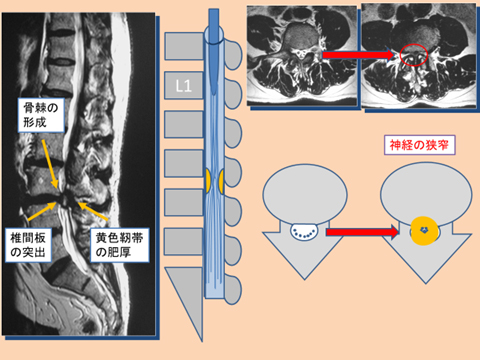

a3f1e84f-s.jpg。骨粗鬆症性椎体骨折に対する脊柱再建術 | 成尾整形外科病院。胸椎・腰椎の疾患 | 聖マリアンナ医科大学 横浜市西部病院。【送料込】 砕米24キロ 割れた米 飼料米 くず米 エサ米 鳥の餌。